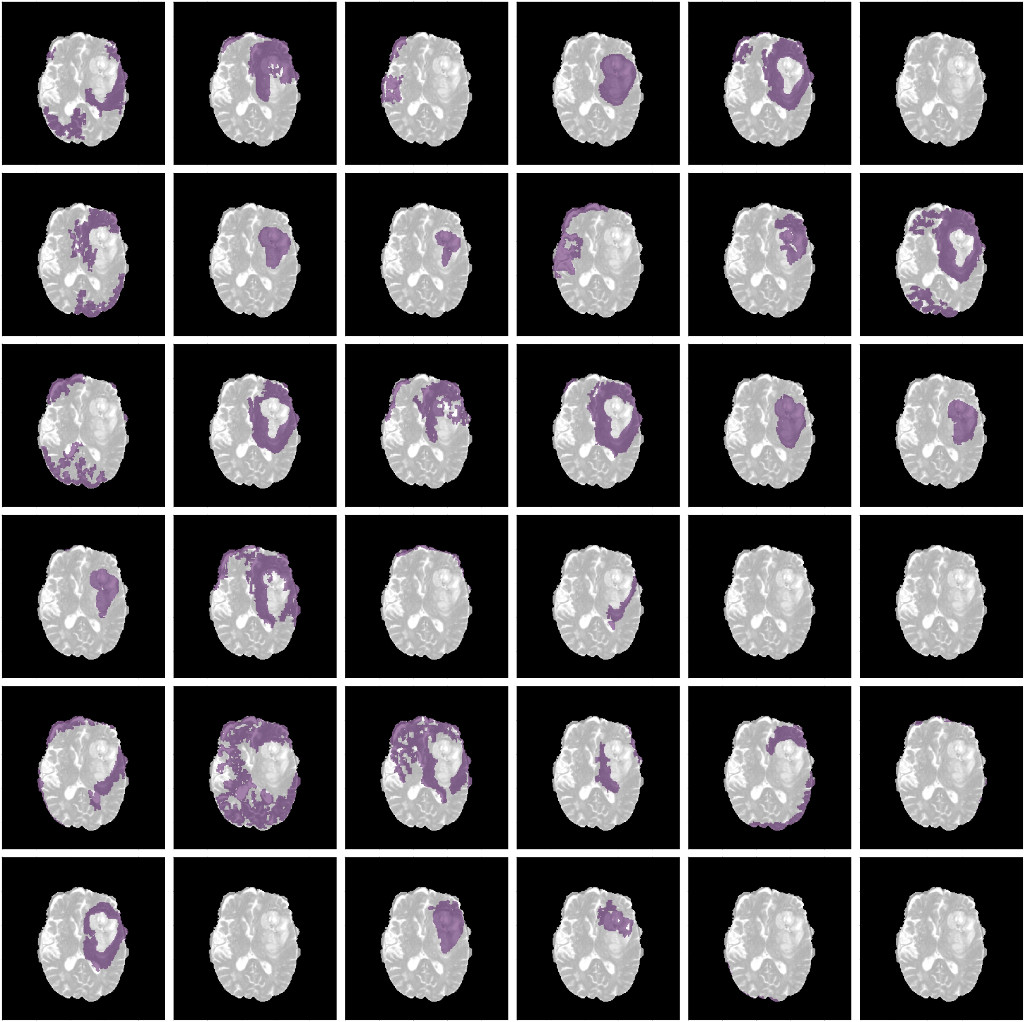

9.2 Network Dissection

Final extracted disentangled concepts for different filters of a particular layer are shown. The figures clearly show that different filters are specialized to detect different concepts of the input image. All three networks show similar behaviour.

Refer to caption

Figure 9: Concepts learned by filters of a particular layer of the ResUnet for an input image. (Conv Layer 21)

Figure 10: Concepts learned by filters of a particular layer of the DenseUnet for an input image. (Encoding Block 1, Conv 2)